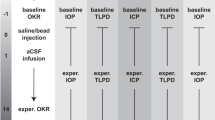

The translaminar autonomous system maintained human donor posterior eye cups for 14 days

The pressurized TAS model (Supplementary Fig. 1) successfully maintained human donor posterior eye cups for 14 days (Fig. 1) (N = 3 eyes/group). This model has been previously described in detail regarding the successful individual maintenance of simulated ICP and IOP chamber pressure modulations (Supplementary Fig. 1a)23. Here, the model was adapted to simulate ICP and IOP under microgravity conditions as well as the tortuosity of the ON observed after LDSF (Supplementary Fig. 1b)24. Representative images (Supplementary Fig. 1c, d) depicting the actual 3D printed models and a representative human posterior eye segment being placed within the TAS model is shown. To improve the accuracy of the pressure settings, we built individualized pumps for each ICP and IOP chamber. This allowed us to modulate the pressures to a 1 mmHg degree of accuracy by manually adjusting the flow rate of our perfusion medium. Some groups required several days before reaching a stable pressure, but pressures were relatively consistent once equilibrium was reached.

Graphical representation of sum of mean TLPD (difference in mmHg of IOP-ICP every 24 h) pressures being maintained for (a) Group 1, (b) Group 2, (c) Group 3, (d) Group 4, (e) Group 5 and (f) Group 6. ICP intracranial pressure, IOP intraocular pressure, TLPD translaminar pressure difference, N = 3. Data are presented as mean ± standard error of the mean and P < 0.05 was considered statistically significant.

The various pressure conditions were determined from previously published data5,7,8,9,10. On Earth, ICP is lower when seated in the 90° upright posture compared to supine (seated, 4 ± 1 vs. supine, 15 ± 2 mmHg). On the contrary, under conditions of acute zero gravity, ICP is reduced but not to the levels of an upright position on Earth (supine, 17 ± 2 vs. microgravity, 13 ± 2 mmHg). The prolonged exposure to microgravity does not cause a pathogenic elevation in ICP (supine, 15 ± 2 vs. 24 h head‐down tilt, 15 ± 4 mmHg) but instead it prevents the normal lowering of ICP when upright17. This chronic, mild elevation in ICP, does not subside under microgravity conditions and can adversely affect eye structure and function during prolonged space flight22. In addition to ICP, the IOP is also seen as instantaneously elevated during parabolic flights under acute microgravity exposure. A 5 mmHg increase in IOP is observed through the free-fall phase of parabolic flight from a mean baseline value of 12 mmHg to 19 mmHg within 20 s of exposure to microgravity25. It has been shown that during short-duration flights, the IOP initially elevates during the first few days and then drops below preflight levels on return to Earth26. Under stimulation studies, IOP during a 6° HDT bed rest study for 7 days has shown an initial immediate rise in IOP after which there has been a slight and progressive decrease by 1.3 mmHg27. Variable reports on IOP changes during 6° and 10° HDT in humans have shown variable responses with increase in IOP and ICP through short-term studies27,28. Although long-term monitoring of HDT has not been performed in humans.

Based on this data, the following pressure groups were identified: group 1 (12:16 mmHg, ICP: IOP, Fig. 1a), group 2 (15:16 mmHg, ICP: IOP, Fig. 1b), group 3 (12:21 mmHg for 7 days and then 12:16 mmHg for 7 days, ICP: IOP, Fig. 1c), group 4 (21:16 mmHg, ICP: IOP, Fig. 1d), group 5 (15:16 mmHg, 6 degree optic nerve tilt, ICP: IOP, Fig. 1e) and group 6 (15:16 mmHg, 10 degree optic nerve tilt, ICP: IOP, Fig. 1f). We were able to maintain relatively consistent pressures for each of the 6 groups under various ICP: IOP conditions (Fig. 1). We took all average translaminar pressure difference (TLPD) (difference in mean of IOP-ICP) for each group (N = 3) and graphed them for each 24-hour timepoint (Fig. 1). Group 3 has been divided into two pressures for the IOP chamber to reflect the acute elevation of IOP during initial flight stages and the subsequent return to normal physiological levels (Fig. 1c). In addition, group 1 (12:16 mmHg, ICP: IOP) (Fig. 1a) reflects the average mean Earth ICP and IOP pressures but at constant pressures.